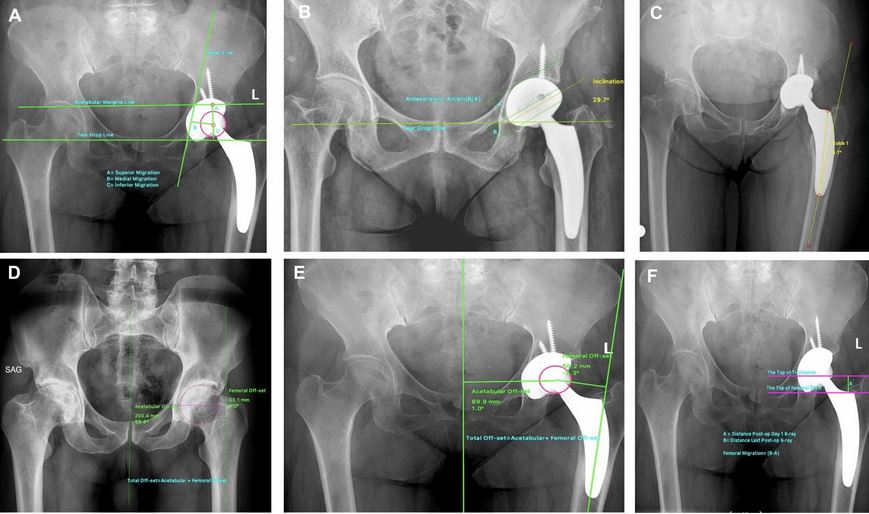

Comparative Study Of The Short Term Results Of Short Stem Cementless Total Hip Arthroplasty And Standard Stem Cementless Arthroplasty

Mahmoud Khairy, Ahmed Hassaan, Ayman Soliman

Biolife. 7(1), 01-08